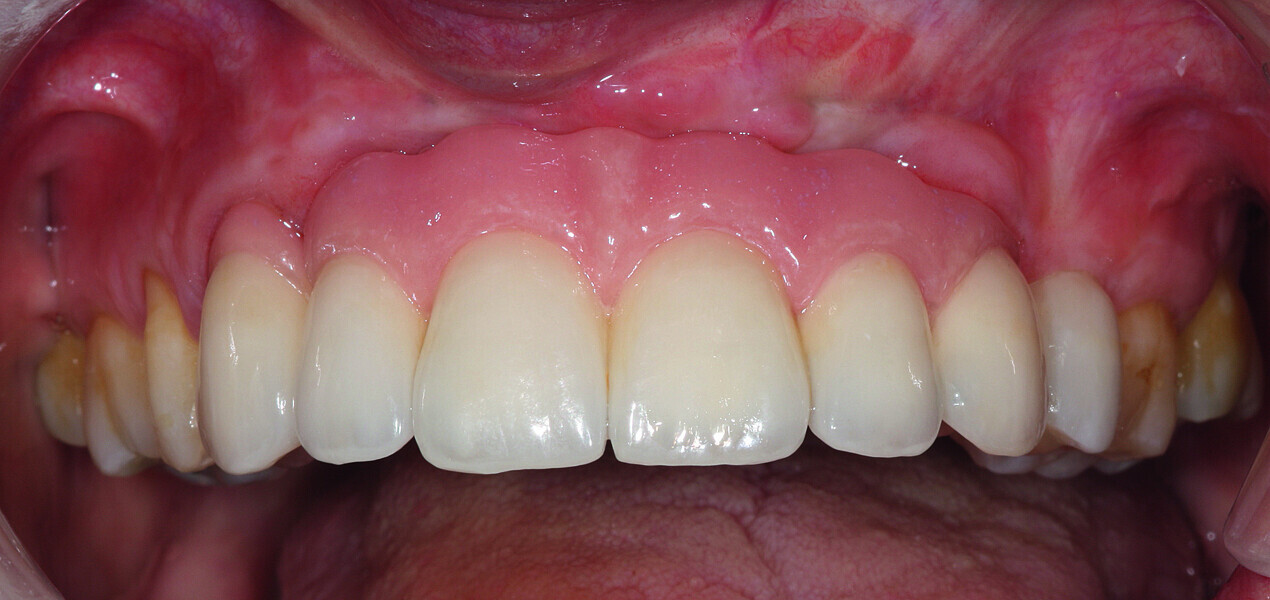

Fig. 38: Final cosmetic check-up showing correct lip support with the new extremely reduced false gingiva.

Fig. 39: Final cosmetic check-up showing correct lip support with the new extremely reduced false gingiva.